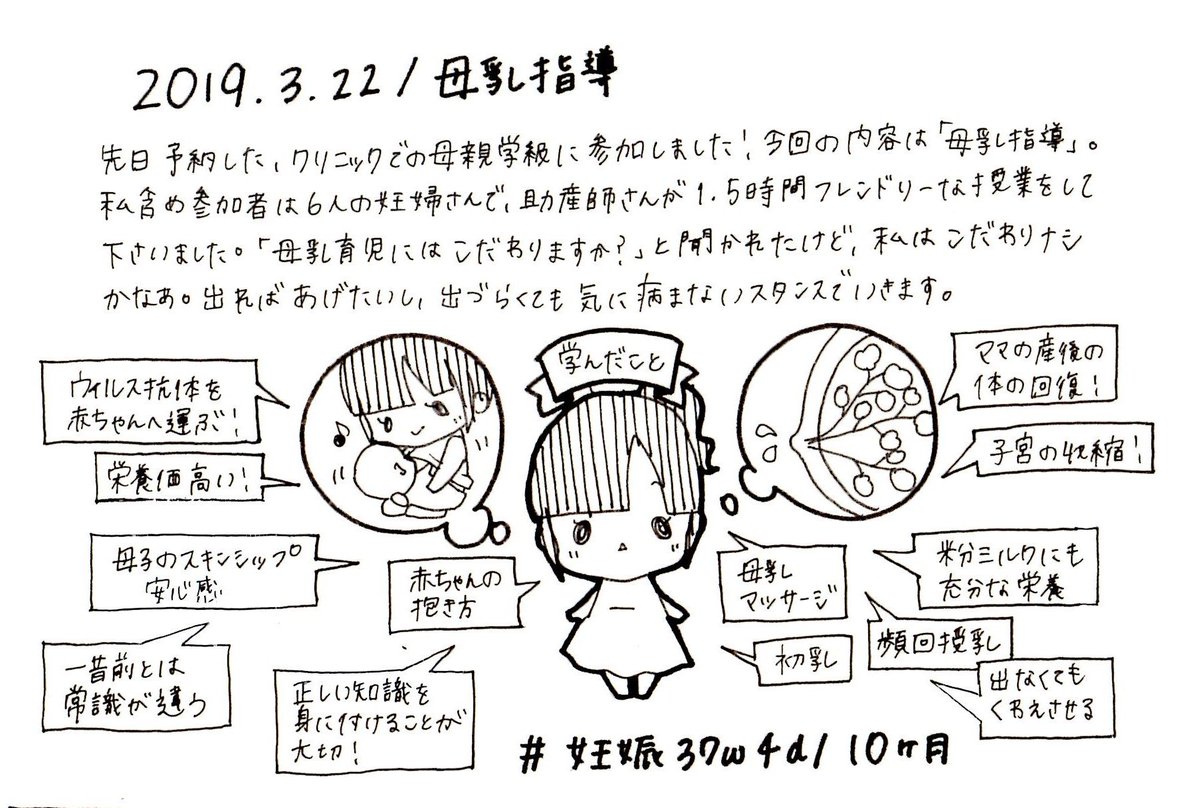

2019.3.22 産院での母親学級に!母乳についての授業でした。母乳育児にこんなにいろんなメリットがあるなんて知らなかった! #育児漫画 #育児日記 #妊娠 #臨月 #妊娠10ヶ月 #正期産 #母親学級 #母乳 #ママ垢さんと繋がりたい #オリジナル漫画 #絵描きさんと繫がりたい pic.twitter.com/85osdosiMB

2019-09-06 21:38:29 拡大

拡大